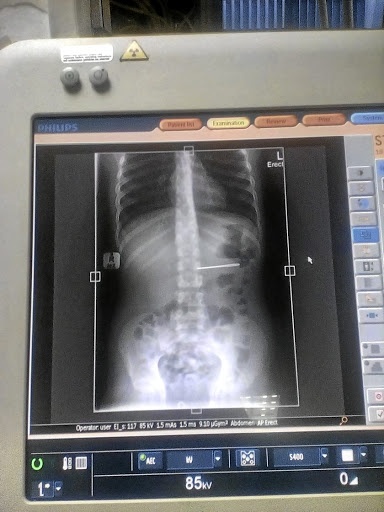

| Hình ảnh chụp X-quang cho thấy chiếc kim nằm trong dạ dày nạn nhân. Ảnh: Timeslive. |